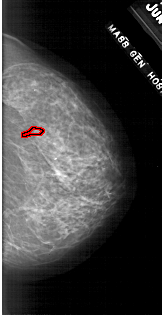

A_1784_1.RIGHT_MLO

RIGHT_MLO LINES 5926 PIXELS_PER_LINE 2836 BITS_PER_PIXEL 12 RESOLUTION 43.5 OVERLAY

FILE: A_1784_1.RIGHT_MLO.OVERLAY

TOTAL_ABNORMALITIES 1

ABNORMALITY 1

LESION_TYPE CALCIFICATION TYPE PLEOMORPHIC DISTRIBUTION CLUSTERED

ASSESSMENT 4

SUBTLETY 2

PATHOLOGY BENIGN

TOTAL_OUTLINES 1

BOUNDARY